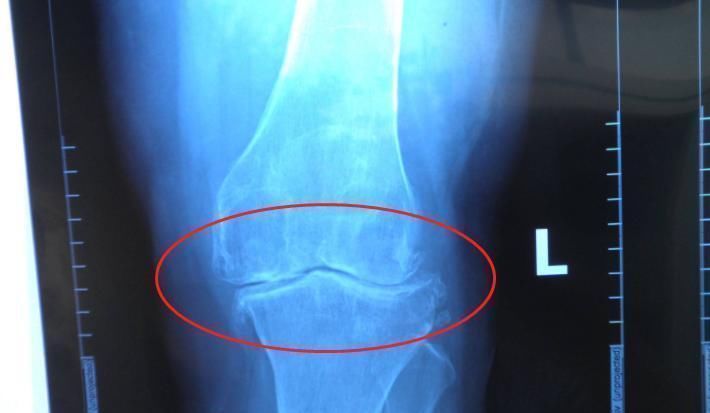

4、骨骺线闭合情况

简单说,骨骺线就是骨与骨之间的一条软组织,当这条软骨没有骨化之前,大家都有继续长高的机会,当骨骺线闭合后,身体停止长高。

同理,男生的身高也受骨骺线闭合情况影响,有研究证明,男生在25岁之前都有继续长高的可能性,但前提是,骨骺线没有闭合,抓住长高的最后一丝希望,或许身高还能再窜一窜。